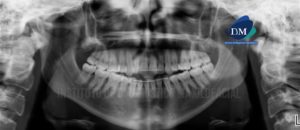

Paciente de sexo femenino de 40 años de edad acude al Instituto de Diagnóstico Maxilofacial para evaluación imagenológica de terceras molares. A la evaluación de